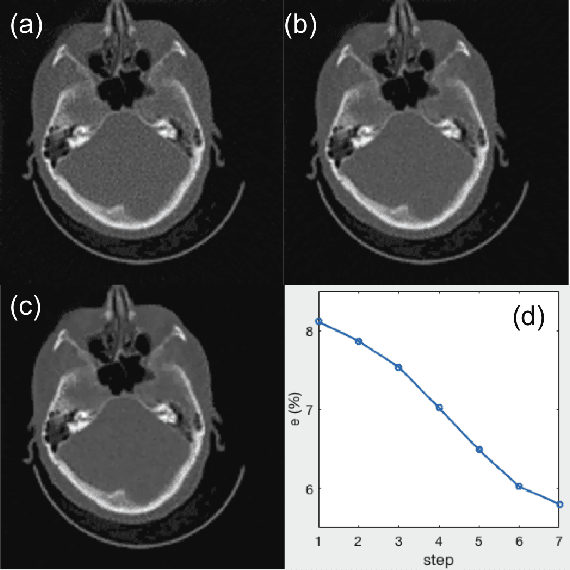

Abstract:A number of image-processing problems can be formulated as optimization problems. The objective function typically contains several terms specifically designed for different purposes. Parameters in front of these terms are used to control the relative weights among them. It is of critical importance to tune these parameters, as quality of the solution depends on their values. Tuning parameter is a relatively straightforward task for a human, as one can intelligently determine the direction of parameter adjustment based on the solution quality. Yet manual parameter tuning is not only tedious in many cases, but becomes impractical when a number of parameters exist in a problem. Aiming at solving this problem, this paper proposes an approach that employs deep reinforcement learning to train a system that can automatically adjust parameters in a human-like manner. We demonstrate our idea in an example problem of optimization-based iterative CT reconstruction with a pixel-wise total-variation regularization term. We set up a parameter tuning policy network (PTPN), which maps an CT image patch to an output that specifies the direction and amplitude by which the parameter at the patch center is adjusted. We train the PTPN via an end-to-end reinforcement learning procedure. We demonstrate that under the guidance of the trained PTPN for parameter tuning at each pixel, reconstructed CT images attain quality similar or better than in those reconstructed with manually tuned parameters.